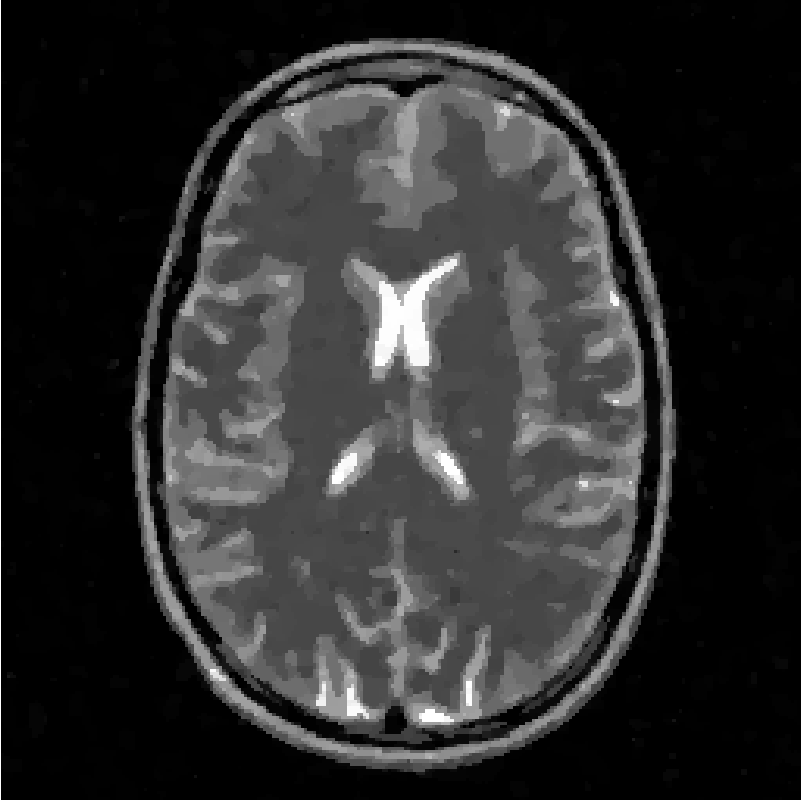

4.3 Comparison with other methods

In this paragraph we compare the FNCR algorithm with the very efficient algorithm IL recently proposed in the literature [13], where the authors minimize a class of concave sparse metrics in a general DCA-based CS framework. Both synthetic and real MRI data are tested. In [13] the authors test their method on T1 image with radial mask and they show that a perfect () can be obtained with 7 rays. Performing the same test FNCR also reaches in comparable times.

Then we applied both methods to the T2 test image both methods with mask and we obtained perfect reconstructions with sampled projections, while decreasing the projections to IL obtains and FNCR reaches (see Figure 7).

Concerning the real MRI data we compare IL and FNCR algorithms in the reconstructions of the brain image (T3 test), represented in figure 8. We report in table 6 the results obtained by reconstructing the noiseless data undersampled by , , masks.

From the table, we see that FNCR always outperforms IL.

In figure 10 we show the FCNR and IL reconstructions in case of mask and .